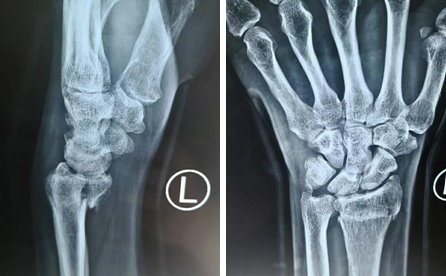

周大爷到达医院后,拍了片子等结果。医生告诉他,“您这是左桡骨远端骨折,关节面碎裂。”周大爷一听骨折了,自己是个左撇子,平时干啥都用左手,心想这可咋办?医生也面带难色告诉周大爷:“桡骨远端骨折不累及关节就好办了,累及关节面就难了,没有关节镜就很难拼凑关节面,只能从侧面固定。”周大爷一听没有做手腕手术的关节镜,手术恢复也差,一时不知如何是好。医生最后对其予以手法复位后夹板外固定,说慢慢恢复吧,效果可能不太好。

手术时间不长,全程大概3小时。齐主任用放大10倍的腕关节镜探查关节面,关节镜下辅助复位,撬拨拼凑,植骨钢板内固定,手术非常顺利。